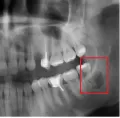

В подростковом возрасте мне сделали резекцию передних зубов из-за кисты. Но спустя примерно 15 лет над зубом образовался, на ощупь, шарик и очень неприятное напряжение под зубом. Я пошла к врачу, он отправил на снимок, но так и не смог мне помочь, и отправил к другому стоматологу, но попасть к нему я так и не смогла.

У вас так называемый рецидив. Обратитесь к хирургу, думаю, данный зуб придется удалить.